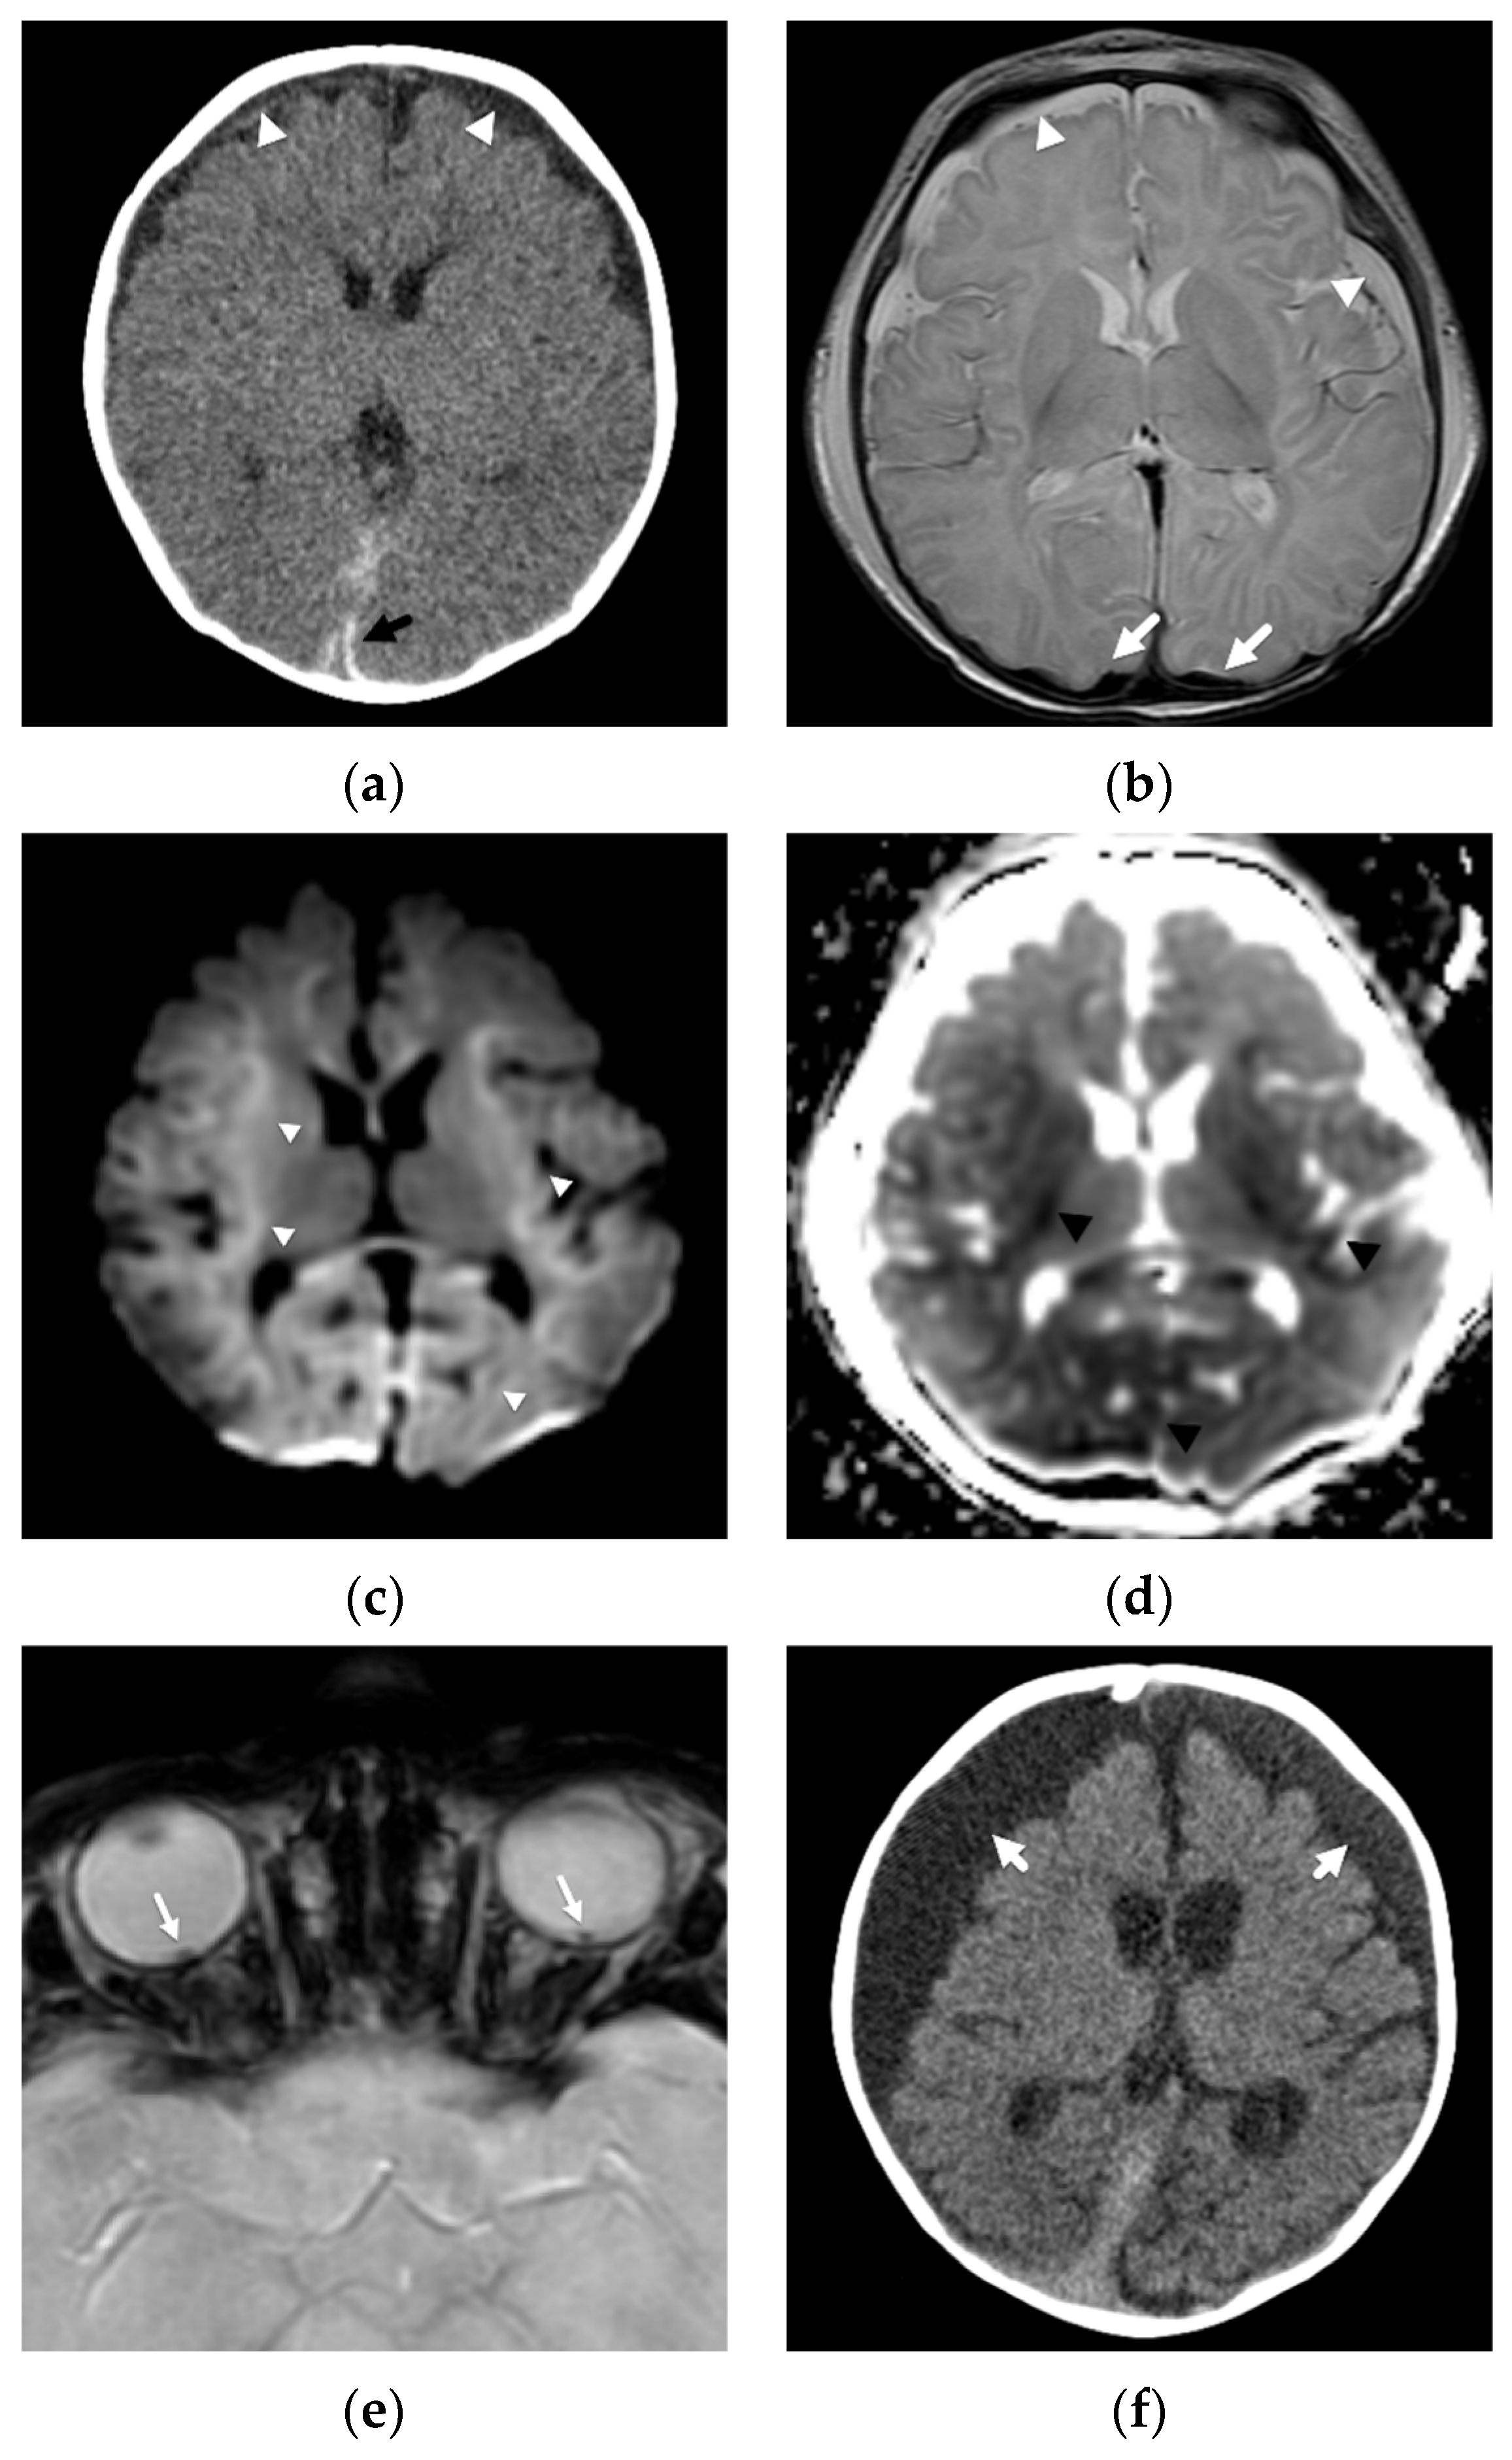

In another study, Zimmerman et al. [25] evaluated DWI in 33 abused infants and young children. The most common pattern of parenchymal insult, found in 13/33 (39%) patients, was of diffuse, restricted diffusion of the supratentorial cortex and white matter. Combined with their second most common pattern, which was present in 12/33 (36%), that of a more watershed or border zone distribution of restricted diffusion with primarily supratentorial but also infratentorial involvement, almost three-quarters of their patients had parenchymal imaging patterns suggesting diffuse hypoxic-ischemic injury/insult and resulting in permanent brain injury. These areas of restricted diffusion were not limited to isolated vascular distributions and were more extensive than focal impact or contusional injuries Figure 2.

Figure 2.

Diffuse, bilateral hemispheric attenuation abnormality in a 3-month-old male presenting in status epilepticus with multifocal facial, extremity, and trunk bruises. (a) Initial axial noncontrast head CT image with diffuse, abnormal attenuation throughout both cerebral hemispheres (white arrowheads); (b) coronal noncontrast CT image shows thin subdural hemorrhage along the left tentorial leaflet (white arrow); (c) coronal reconstruction bone algorithm image from an abdominal CT at presentation shows healing, bilateral posterior rib fractures (black arrowheads); (d) axial T2-weighted image on day 4 demonstrates diffuse, hemispheric loss of gray-white matter differentiation (black arrowheads); (e) axial b-1000 diffusion-weighted image demonstrates diffuse areas of abnormal, restricted diffusion (black arrows) in both cerebral hemispheres consistent with cytotoxic edema/hypoxic-ischemic injury; (f) apparent diffusion coefficient image shows corresponding regions of diffusion restriction predominantly in cortical and subcortical regions of both cerebral hemispheres (black arrows).